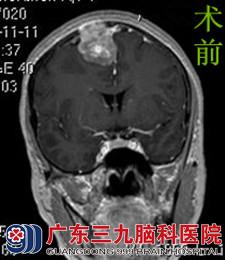

为进一步治疗,罗女士来到广东三九脑科医院综合神经外科。行头颅MR检查提示右侧额部镰旁示一团块状站位性病变,大小约2.98*2.82*3.78cm,病变累及颅骨。行头颅CTA检查提示病变侵犯临近颅骨,供血较丰富,内示稍增粗的血管影,周围示较多血管缠绕,临近上矢状窦轻度受压移位。完善术前检查后,由鲁明主任主刀,在全麻下行右侧额部大脑镰旁脑膜瘤切除术。术中可见肿瘤明显侵犯至颅骨表面,位于额部,侵犯矢状窦,呈灰白色胶状,质地韧,血运一般,予镜下全切,手术顺利结束。术后经过专科治疗护理,罗女士康复出院。术后病理结果:过渡型脑膜瘤。